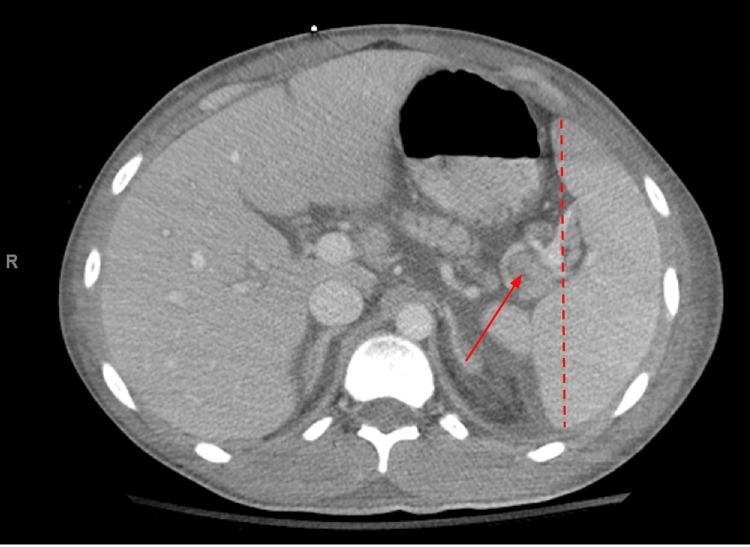

Evans syndrome (ES) is a condition that describes the development of multiple cytopenias, including autoimmune hemolytic anemia (AIHA), immune thrombocytopenia (ITP), and autoimmune neutropenia (AIN). ES can be idiopathic or caused by an underlying condition, known as secondary ES. While secondary ES is associated with increased morbidity and mortality, any diagnosis of ES confers a poor prognosis. In this case report, we describe a young male patient diagnosed with systemic lupus erythematosus (SLE) and secondary ES that was complicated by multiple relapses and subsequent infections, bleeding events, and thrombotic events that ultimately led to the passing of the patient.

伊文斯综合征(ES)是一种描述多种血细胞减少症发展情况的病症,包括自身免疫性溶血性贫血(AIHA)、免疫性血小板减少症(ITP)和自身免疫性中性粒细胞减少症(AIN)。ES可以是特发性的,也可由潜在病症引起,后者称为继发性ES。虽然继发性ES与发病率和死亡率增加相关,但任何ES诊断都预示着预后不良。在本病例报告中,我们描述了一名年轻男性患者,他被诊断患有系统性红斑狼疮(SLE)和继发性ES,该病症并发多次复发以及随后的感染、出血事件和血栓形成事件,最终导致患者死亡。